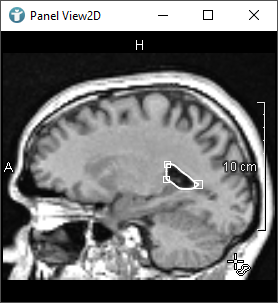

CSOs can also be grouped together. The following image shows two different CSOGroups. Groups can be used to organize CSOs, in this case to distinguish the CSOs of the right and the left lung. Here you can find more information about CSOGroups.